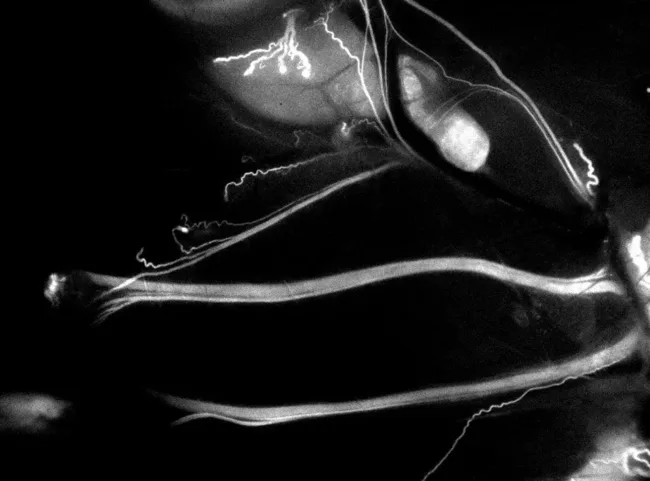

The promise of LGW16-03 is its potential to make these structures visible in a dynamic surgical field. While fluorescence-guided surgery is well established in oncology (notably in lymphatic and tumor visualization), the extension into nerve tissue is a comparatively uncharted application. The molecule’s selective binding to nerve tissues and its compatibility with existing near-infrared imaging systems give it a chance to integrate into surgical workflows without requiring new infrastructure. This integration will be a critical factor in eventual adoption.

Trace Biosciences, a clinical-stage biotechnology company focused on nerve-targeted imaging agents, has received Investigational New Drug (IND) clearance from the U.S. Food and Drug Administration for LGW16-03, its first fluorescent imaging compound designed to highlight peripheral nerves during surgery. This regulatory milestone authorizes the company to launch first-in-human trials of the compound, marketed as NerveTrace Dx, which emits a near-infrared signal to allow real-time visualization of nerves intraoperatively.